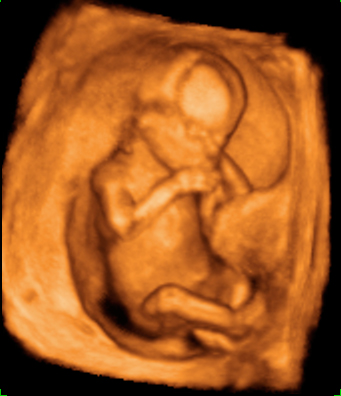

En la ecografía en 3D del feto en la 15ª semana de gestación se aprecia su anatomía. Es casi como la de un bebé a punto de nacer. Mide alrededor de los 10 cm y pesa unos 50 gramos.

Imagen de un feto de 15 semanas en ecografía 3D

La imagen es impresionante: la apariencia de este feto, de 15 semanas, es la de un niño que no le queda mucho tiempo de gestación para nacer. Cabeza, tronco, brazos y piernas se perfilan perfectamente en la ecografía del primer trimestre. Se lleva la mano a la boca mientras descansa apoyado en la pared uterina, como es normal es esta edad gestacional. La mayoría de las madres no se imagina que los fetos están tan "acabados" con apenas cuatro meses de embarazo.